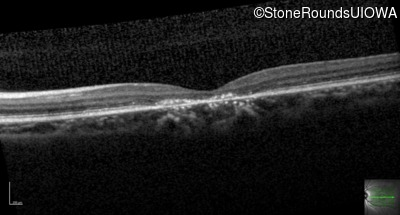

OD

OS

20/160

OCT Stack

20/32 +1